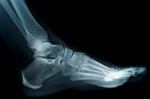

Today I tried three different pairs of shoes

before I strapped these sandals on my feet.

I’ll pay for it on path or stairs or street.

When I select the proper shoes to put

around my feet, that’s happiness enough.